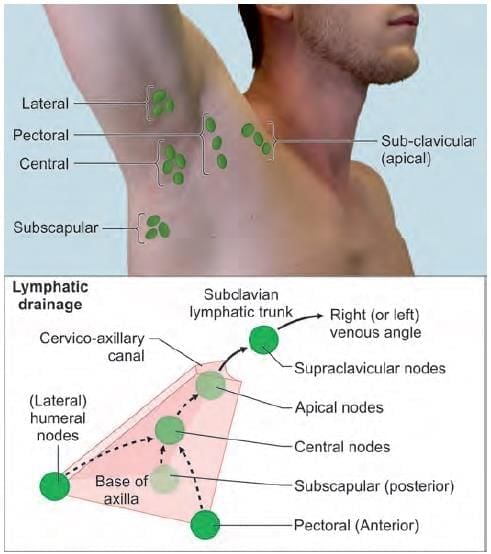

Mention the nerve supply of the marked muscle: (INI-CET May 2022)